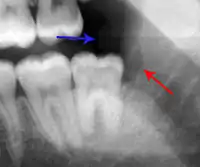

- Radiographs utilized to find dental caries and bone loss laterally or at the apex.

The periodontal ligament becomes inflamed and there may be pain when biting or tapping on the tooth. On an X-ray, bone resorption appears as a radiolucent area around the end of the root, although this does not manifest immediately.[10]: 228 Acute apical periodontitis is characterized by well-localized, spontaneous, persistent, moderate to severe pain.[6]: 125–135 The alveolar process may be tender to palpation over the roots. The tooth may be raised in the socket and feel more prominent than the adjacent teeth.[6]: 125–135

Apical periodontitis is acute or chronic inflammation around the apex of a tooth caused by an immune response to bacteria within an infected pulp.[20] It does not occur because of pulp necrosis, meaning that a tooth that tests as if it's alive (vital) may cause apical periodontitis, and a pulp which has become non-vital due to a sterile, non-infectious processes (such as trauma) may not cause any apical periodontitis.[10]: 225 Bacterial cytotoxins reach the region around the roots of the tooth via the apical foramina and lateral canals, causing vasodilation, sensitization of nerves, osteolysis (bone resorption) and potentially abscess or cyst formation.[10]: 228